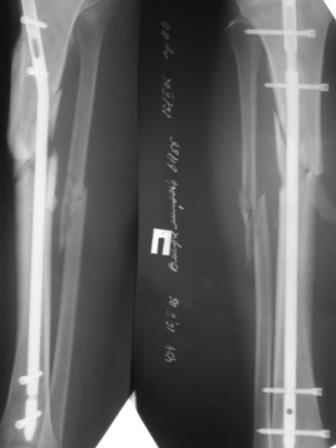

Уважаемые коллеги! Больной лечился два месяца назад с ипсилатеральными переломами бедра и голени.

Голень лечили тем что было(стержень сплошной 9мм), при поступлении - ротационная подвижность в с/3 голени. Дистально поставили еще один сагитальный винт. Ротационная подвижность уменьшилась, но не полностью . В чем причина? тактика?

Вообще, к двум месяцам пора бы срастаться начинать, а не подвижность демонстрировать. Хотя перелом бамперный, похоже. И стержень введен как раз с типипчными проблемами для переломов верхней трети - вальгус и заднее смещение дистального отломка. Ротационная подвижность за счет люфта винтов может быть градусов 10, наверно. Завтра попробуем померять на макете.

Уважаемый Антон Коваленко! Задержка консолидаци большеберцовой кости при ипслатеральных переломах бедра и голени довольно распространенное явление, его отмечают очень многие авторы. В Вашем случае остеосинтез UTN, наверное, был не самым лучшим выбором, учитывая локализацию перелома. И, раз уж Вы остановились на нем, логично было бы синтезировать малоберцовую кость, так как оба перелома находятся практически на одном уровне. Считаю, что было бы не обоснованно менять тактику лечения (добавление аппарата внешней фиксаци или пластины), как рекомендовали коллеги, на таких сроках. Я бы тоже использовал внешнюю фиксацию 3 - 4 нед, с последующим рентген контролем. Думаю, перелом срастется. Кстати, Вы не указали возраст пациента, от этого тоже зависит тактика и прогноз. С уважением,Д. Широков.

уважаемый Антон!Хотелось бы поделиться своими соображениями по поводу Вашей проблемы.судя по снимку перелом высокоэнергетический.Видимо в момент удара произошла девитализация фрагментов.На подобную возможность указывает папаша Мюллер в своем бессмертном "руководстве по внутреннему остеосинтезу":)Кроме того мне кажется,что в данном случае стабильность остеосинтеза сомнительна. Я думаю,что в данном случае лечить надо было АВФ или пластиной с первичной костной пластикой.У меня был подобный случай.Справился АВФ с остеоперфорацией